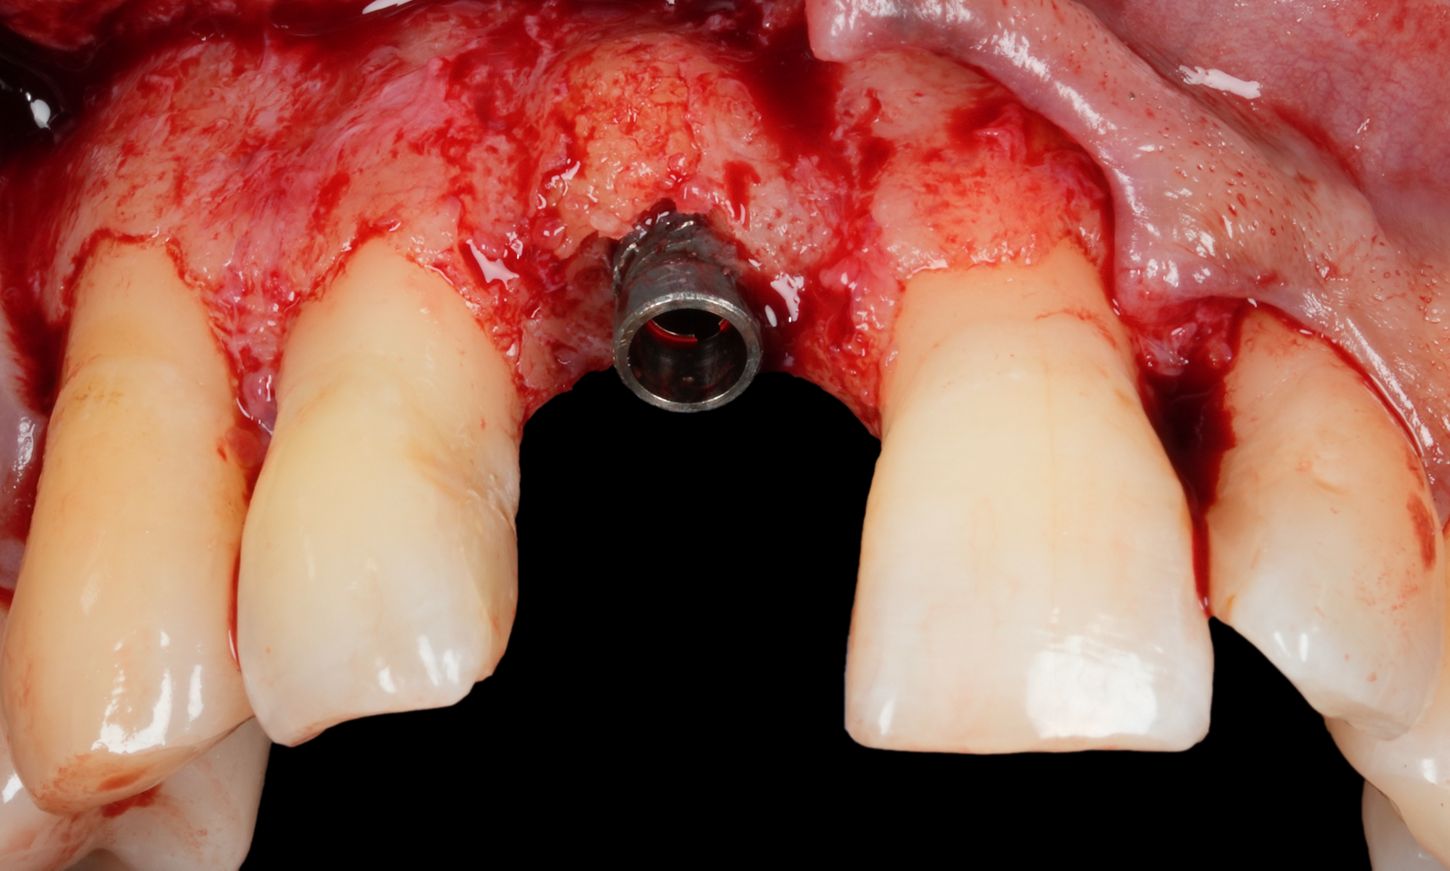

A full-thickness mucoperiosteal flap was elevated to expose the affected implant and the surrounding bone defect. The clinical examination confirmed the presence of a mixed horizontal and crater-like peri-implant bone defect, as previously noted on radiographs (Fig. 9).

Fig. 9

The exposed implant surface was thoroughly decontaminated using the GalvoSurge® Dental Implant Cleaning System. This electrochemical cleaning technique operates by generating hydrogen bubbles at the implant surface, which mechanically lift and detach biofilm and other contaminants without damaging the titanium microstructure. The process allows for an effective and atraumatic surface decontamination, creating a favorable environment for potential re-osseointegration and regenerative healing (Figs. 10-12).